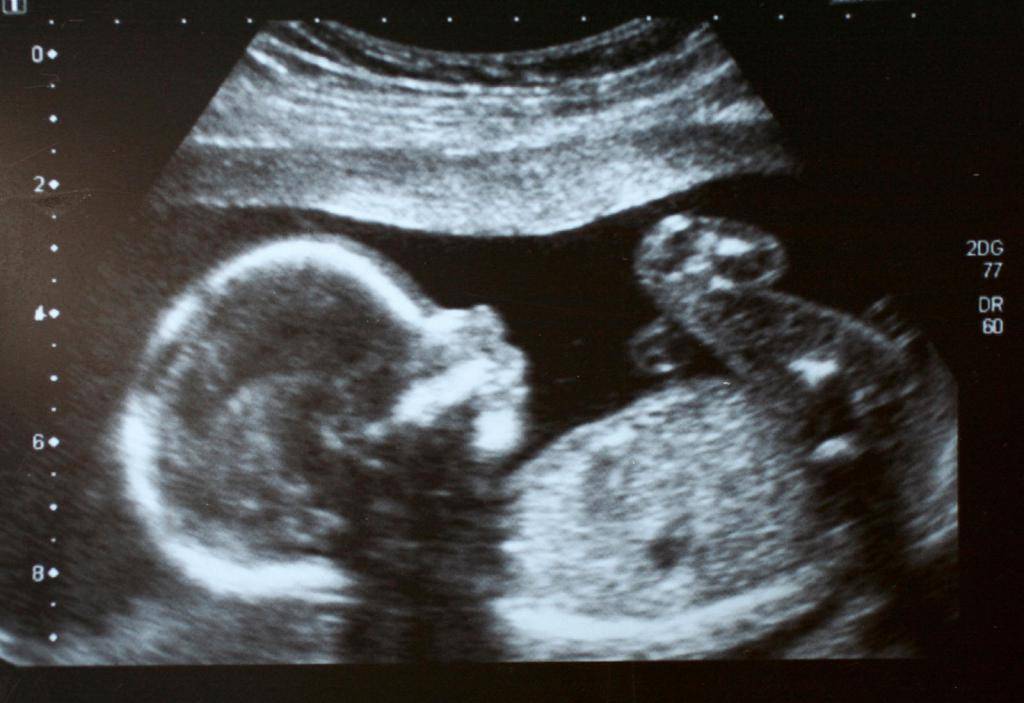

На беременности размеры плода уже достаточно большие. Определяются они во время проведения ультразвукового исследования. Доктор оценивает не только вес и длину туловища малыша, но и проводит исследование важных структур детского тела.

Для удобства оценки полученных клинических показателей специалисты УЗИ применяют специальные таблицы. Эти медицинские документы разработаны для каждой недели беременности. В них внесены нормальные значения основных оцениваемых параметров. Такая таблица, соответствующая сроку 33 недели беременности, представлена ниже:

Во время проведения исследования специалист может также определить и другие клинические параметры. Они являются важными на этом сроке внутриутробного развития.

Одним из таких определяемых клинических параметров является бипариетальный размер. В норме его значения на этом сроке внутриутробного развития плода составляют 7,7-9,1см.

Оценить размер головного мозга также можно при помощи другого клинического критерия, который называется лобно-затылочным размером. В норме данный показатель составляет 9,8-11,6 см. Окружность головы малыша на этом сроке беременности составляет 28,9-33,3 см.

Во время проведения исследования доктор может измерить и другие, не менее важные клинические показатели. Одним из них является окружность живота. В норме значения данного показателя составляют 26,7-32,5 см.

На этом сроке беременности обязательно также оцениваются длины косточек. Так, нормальной длиной бедер у малыша является показатель, равный 5,8-6,8 см. Косточки плеча по длине на этом этапе беременности составляют 5,3-6,3 см.

Ультразвуковое исследование необходимо не только для определения роста и веса, но и для понимания того, что происходит с малышом на 33 неделе беременности. Визуально на экране определяются все размеры от головы до ножек. Данные параметры позволяют определить соответствие развития плода установленному сроку беременности. В частности, измеряют следующие значения (в скобках будут указаны нормы):

- Окружность головы (289-333 мм) и живота (267-325 мм).

- Бипариетальный размер (77-91 мм).

- Лобно-затылочный размер (98-116 мм).

- Носовая кость (8,9-13,9 мм).

- Копчико-теменной размер (на 33 неделе беременности размер плода – около 30 см).

- Измерению подлежит определение длины костей: плечевой (53-63 мм), предплечья (46-54 мм), бедра (58-68 мм), голени (54-62 мм).